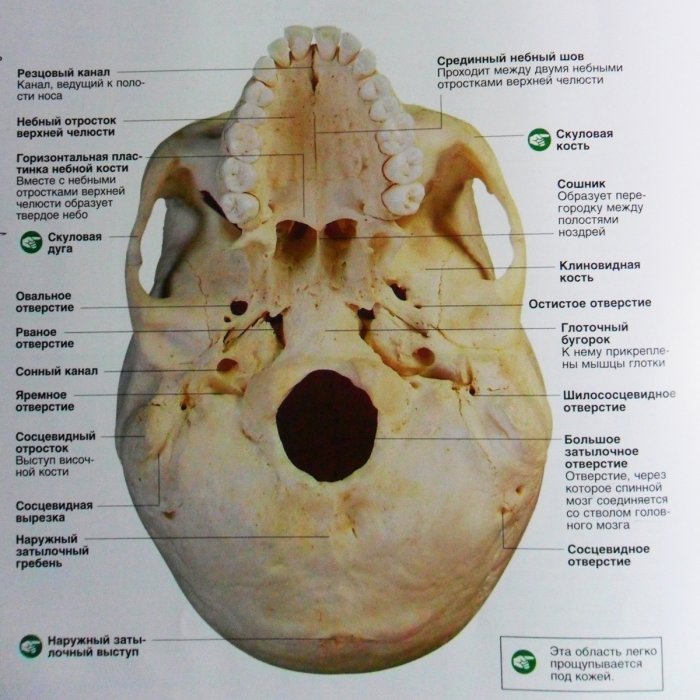

Анатомические детали: Фотографии топографии черепа с нижнего вида

Раздел: Альбом идей